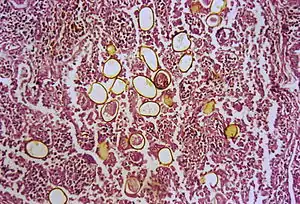

The first human case was seen in 1879 in Taiwan. An autopsy was done and adult trematodes were found in the lungs. The adult flukes have a reddish-brown in color with an ovoid shape. They have two muscular suckers, the first an oral sucker located anteriorly and the second a ventral sucker located mid-body. The adult flukes can live up to 20 years. The eggs are golden brown in color and are asymmetrically ovoid. They have a very thick shell. As seen above, these trematodes have a very complex life cycle with seven distinct phases involving intermediate hosts and humans.[5] These seven phases are outlined as follows: eggs reach fresh water where they develop into miracidia. These penetrate many species of aquatic snails (first intermediate host) where they go through three distinct stages: first sporocysts, then rediae, and finally cercariae, also referred to as the larvae. These larvae released into water and penetrate crabs, crayfish and other crustaceans (second intermediate host). The cercariae situate themselves into the gills, liver and muscles where they further develop into metacercariae. When the parasite-filled crustacean is eaten, the metacercariae hatch in the intestine. These young worms penetrate intestinal wall, peritoneum, the diaphragm and the pleura where they finally reach the lungs. Here they live in pairs, lay eggs that are coughed up in sputum to restart the cycle.[8]